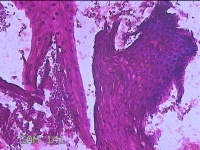

宫颈12点组织

性别

女

年龄

46岁

临床诊断

人乳头瘤病毒感染

一般病史

人乳头瘤病毒其他12高危型阳性

标本名称

大体所见

灰白暗红色组织0.8x0.5x0.2cm一块。